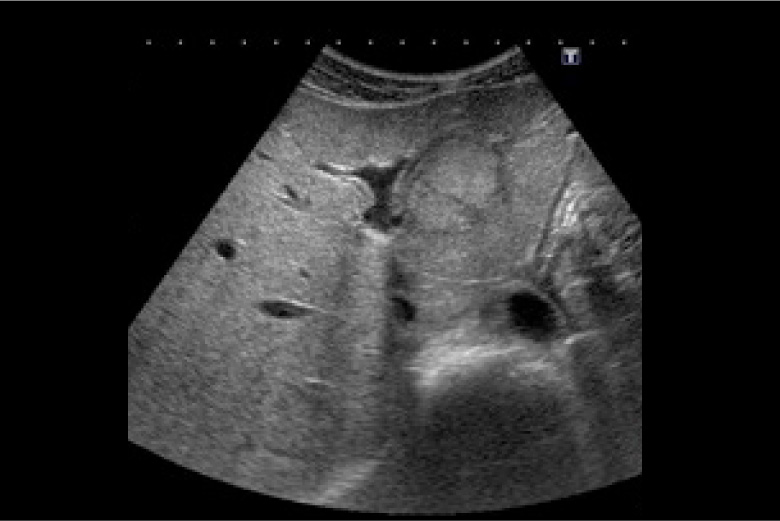

超音波検査

音の性質を利用して生体内の血流状態、及び断層像を描出することができます。腹部、頚部、乳腺、甲状腺、唾液腺などの実質臓器や胃・大腸などの消化管を見ています。無侵襲で痛みはほとんどなく被ばくが有りませんので安心して検査をお受けください。また乳腺領域の検査は女性技師が対応致します。

LOGIQ E9

乳腺腫瘍

肝臓腫瘍